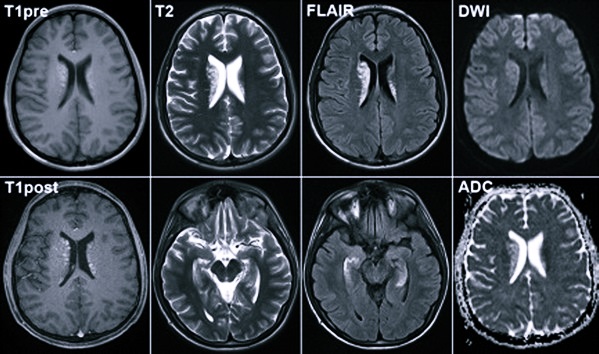

С целью исключения других патологий, протекающих по сходному сценарию, назначаются:

- электроэнцефалография;

- МРТ головного мозга;

- RPR-тест;

- Эхо-ЭГ.